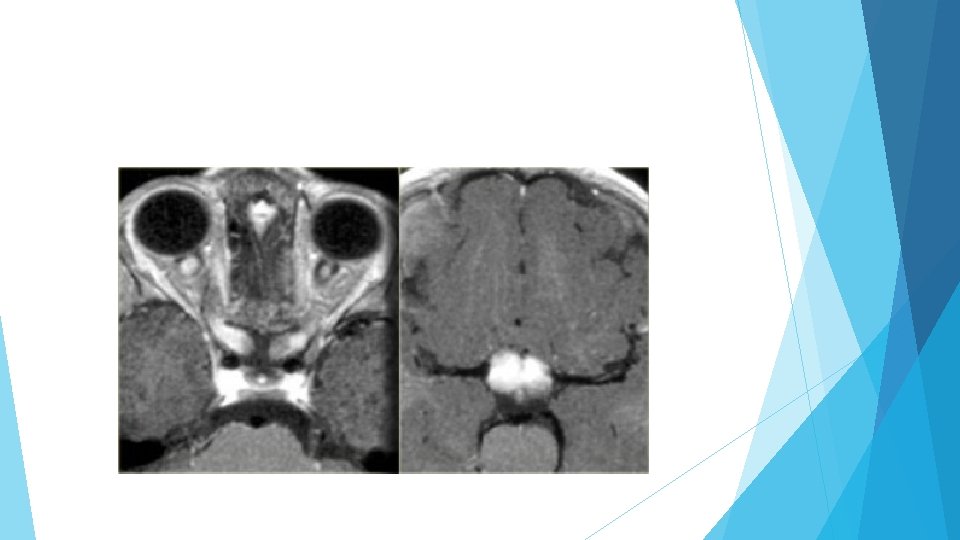

Hypothalamic and chiasmatic gliomas Gliomas can occur in any part of the brain and the optic chiasm is a common location, particularly in patients with neurofibromatosis type 1. A supra sellar mass indistinguishable from optic chiasma. Swelling and edema of optic nerves. 25 % without enhancement

Enhancement of optic nerve meningeal sparing